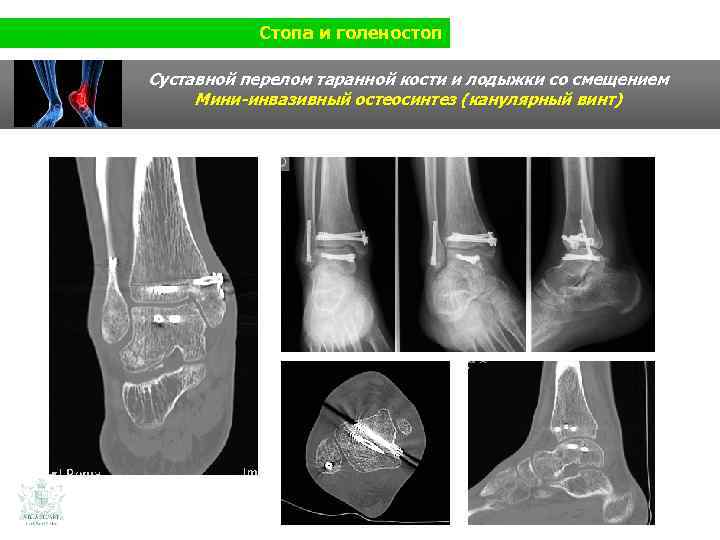

Стопа и голеностоп Клинический случай (стопа и голеностоп) Гимнаст 17 лет Наружный вывих во время спортивных соревнований

Стопа и голеностоп Суставной перелом таранной кости и лодыжки со смещением

Стопа и голеностоп Суставной перелом таранной кости и лодыжки со смещением Мини-инвазивный остеосинтез (канулярный винт)